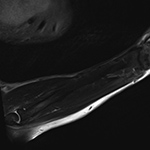

Shading Artifact

Shading artifact is also known as intensity gradient artifact. It occurs due to nonuniformity of the RF field, resulting in loss of voxel signal intensity in regions of low RF strength, and is frequently seen in the setting of imaging with a surface coil (Singh, 2014; Hyde, 1987). This artifact results in variable image contrast, loss of brightness, and subsequent deterioration of image quality due to decreased RF signal strength in structures located further from the coil, and can be corrected by use of an enclosing coil or a larger surface coil (Figure 19). The presence of this artifact should prompt a change in coil used for the examination, such as a dedicated extremity coil, if possible.

Shading Artifact. (A) Incomplete coil coverage results in dark signal obscuring the soft tissues adjacent to the olecranon at the periphery of sagittal STIR image of the forearm in a patient with cellulitis and concern for abscess. (B) Axial T1-weighted post-contrast fat-saturated image obtained following coil repositioning demonstrates abscess (arrow) in the previously obscured region.